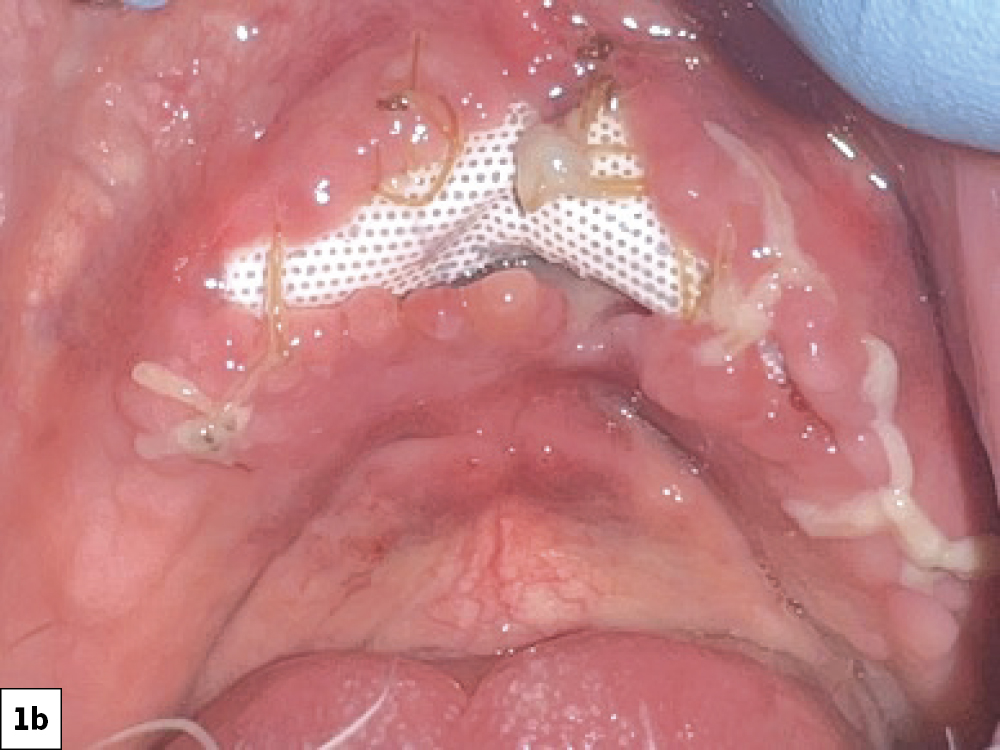

When this wound breakdown occurs, an increased morbidity for dental implant surgery and bone grafting may result because of bacterial contamination (Figs. 1a, 1b). In this article, various techniques and protocols will be discussed to prevent ILO and manage this complication.